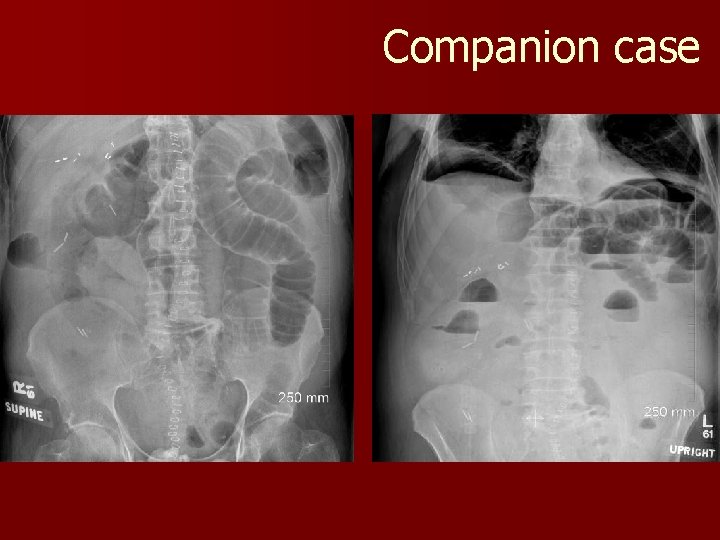

Companion Case

Case 1 n What are the signs of SBO on radiograph? – Dilated and fluid filled loops, “step-ladder” appearance n What SBO? is the difference between ileus and – SBO indicates mechanical obstruction – Ileus is an adynamic state (“bowel shuts down”)